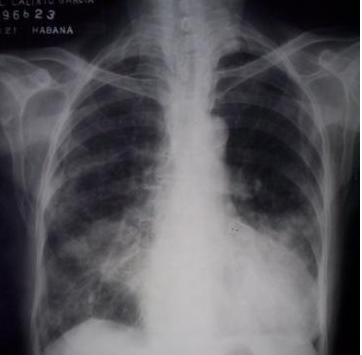

Pneumonia

A broncopneumonia é uma espécie de pneumonia que ataca normalmente os brônquios. Geralmente é uma doença típica nas crianças e nos idosos. Esta condição respiratória provém quase sempre de um catarro mal curado e pela fraqueza das defesas que se esgotaram pela medicação.

A doença dos brônquios grandes passa para os brônquios capilares e invade o tecido pulmonar. O doente tem febre mas esta é irregular e diferente consoante os casos. É frequente que a temperatura baixe à medida que amanhece e, pelo contrário, que aumente bastante pela noite. Claro que, deverá consultar um médico para o examinar, além disso neste artigo de umComo explicamos-lhe algumas recomendações sobre como tratar a broncopneumonia.